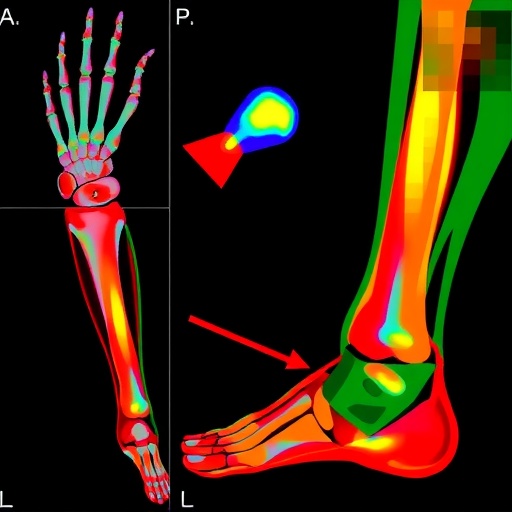

The research itself employed a robust methodology to evaluate the performance of the two AI algorithms. These algorithms were rigorously tested against a set of standard radiographs that depicted a variety of post-traumatic conditions. The study’s findings are poised to set a new benchmark in pediatric radiology, providing empirical evidence of the efficacy of AI support in enhancing diagnostic accuracy. It is essential to understand that the algorithms did not serve as a replacement for human expertise but rather as a complementary tool, potentially increasing the reliability of diagnoses made during the chaotic moments following pediatric trauma.

Moreover, the research highlights the importance of training and refining AI systems to align with the complexities inherent in pediatric cases. The algorithms must not only learn to identify fractures but also understand the variations in growth plates and anatomical differences that can complicate diagnoses. This requires substantial datasets and a commitment to ongoing learning, indicating that the development of AI in medicine is a continual process requiring vigilance and adaptability.